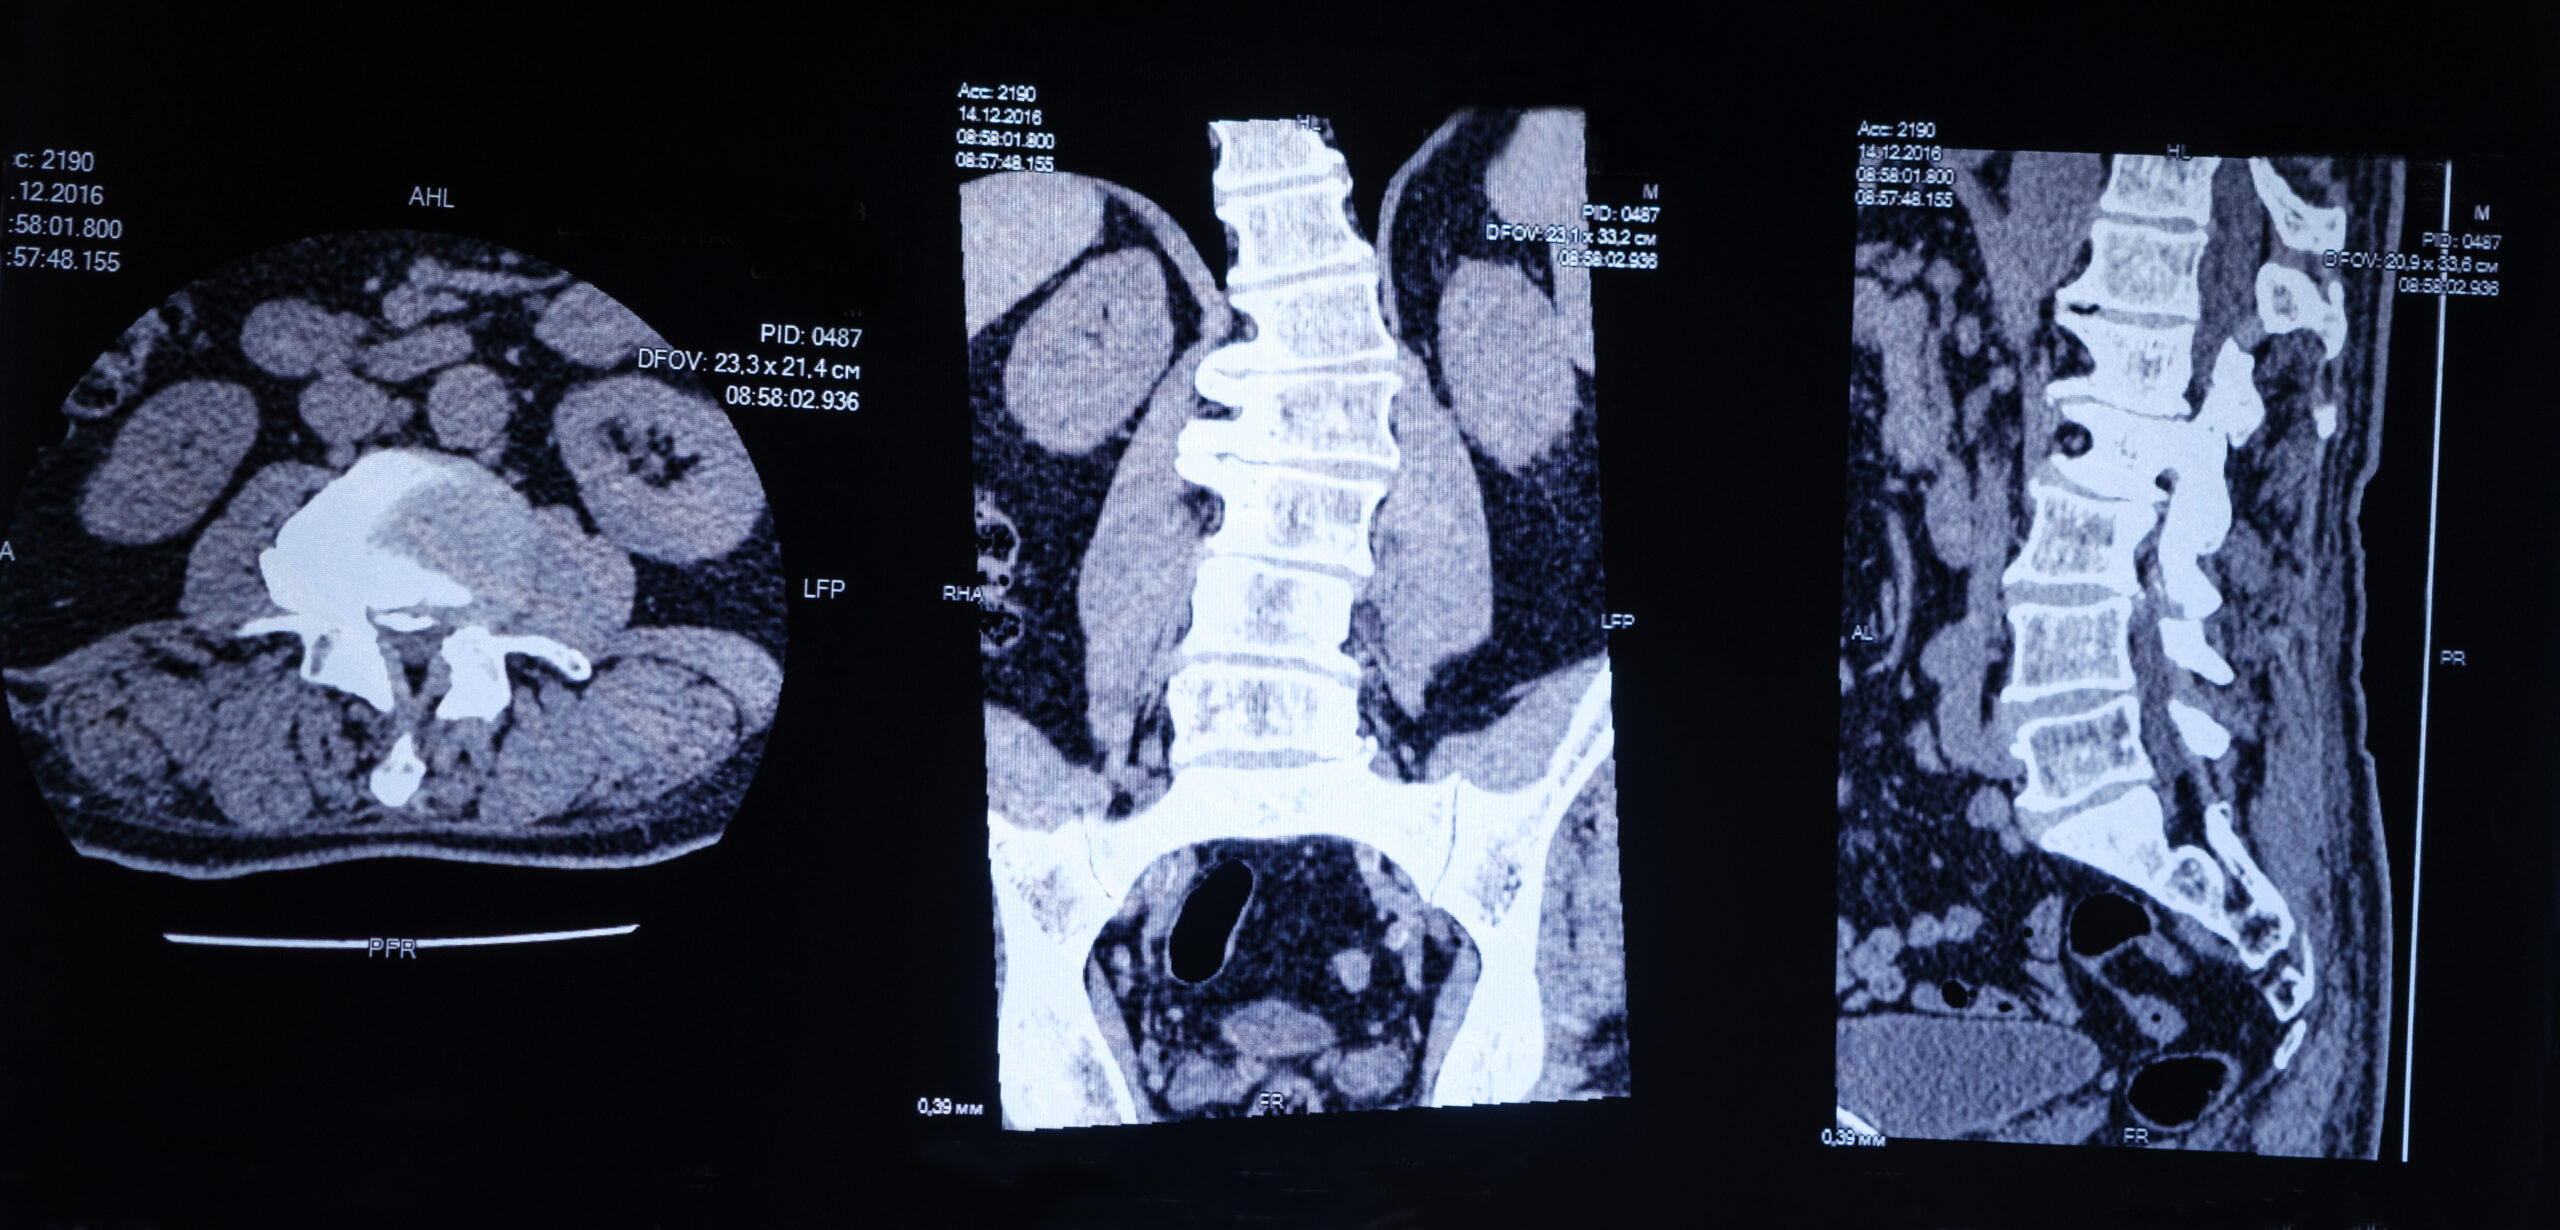

- Access via Kambin’s Triangle: A small incision (less than 1 cm) is made, and the surgeon navigates to the disc space using real-time imaging (fluoroscopy).

- Discectomy and Fusion: The damaged disc is removed and replaced with a cage filled with bone graft material to encourage vertebral fusion.

- Stabilization: Percutaneous pedicle screws may be used for added support depending on the case.